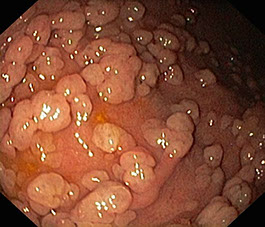

Poliposis Gástrica

Los pólipos gástricos (PG) son lesiones originadas en la mucosa gástrica que se presentan frecuentemente y de manera incidental. Aunque la presencia de pólipos en el estómago es un hecho bastante frecuente, su diagnóstico es generalmente casual, al ser en la mayoría de los casos asintomáticos. El término poliposis gástrica difusa hace referencia a la presencia de múltiples pólipos que cubren gran parte de la mucosa gástrica.

La polipectomía gástrica es una técnica que se realiza por vía oral aplicada al tracto superior digestivo que tiene como finalidad la resección de pólipos.